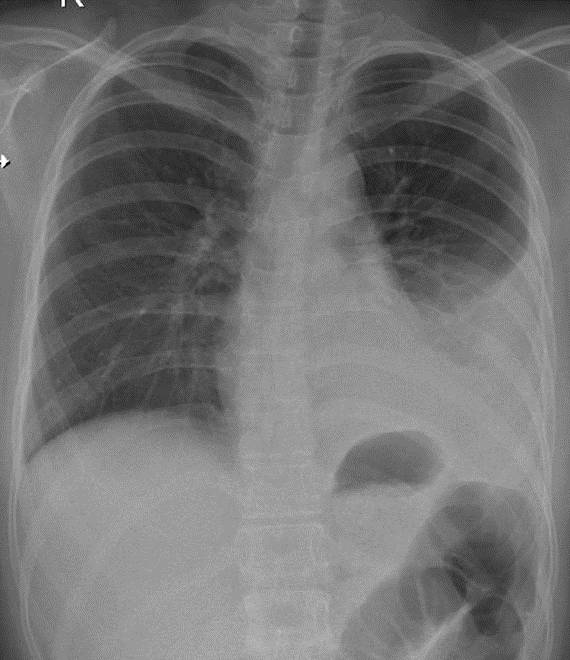

Hãy phân tích tình huống NỮ 25 tuổi -CĐ:Đau tức ngực (T), sốt, sụt cân

1-Tràn dịch màng phổi (T) lượng trung bình